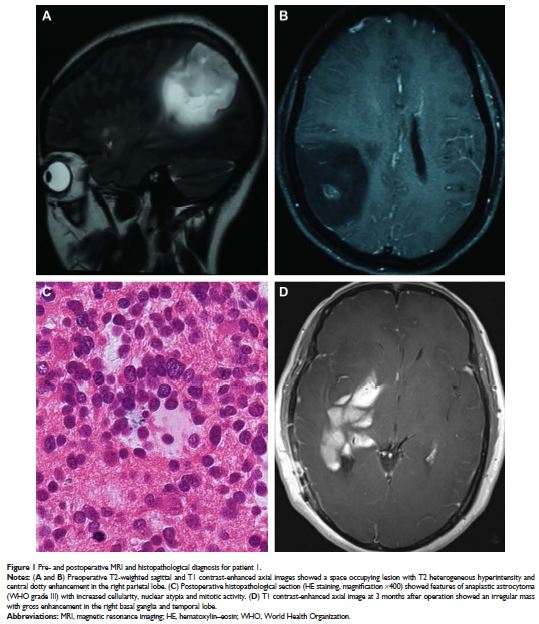

Case Series

- 作者:张红红,陈芳芳,汪志强,吴少雄

- 期刊:OncoTargets and Therapy